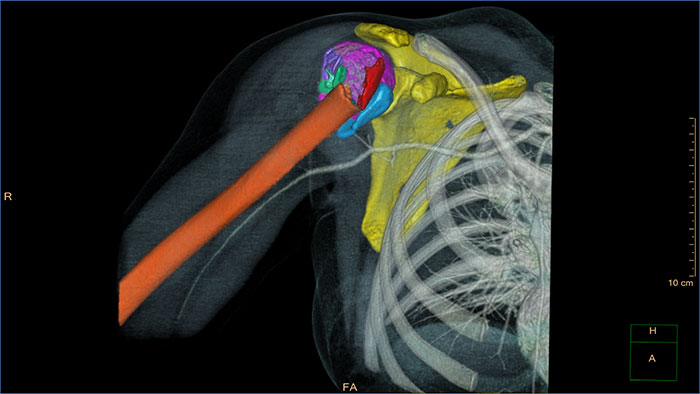

3D Modeling

Streamlined modeling workflow

Allows to view volumetric images of anatomical structures, perform segmentation, edit and combine segmented elements (tissues) into a 3D model.

Benefits

• Studies of CT & MR can be used for creating a single 3D model of the same patient. The application provides tools that allow the user to align between the volumes of interest in the images.

• 3D Modeling batches files can be easily exported in standard formats such as STL, with the option to also provide a 3D PDF as an additional means for results sharing with 3D printing or other services* .

• The user may determine the information related to the exported elements of the 3D model such as smoothness and output mesh size.

• Contours can also be exported as RT Structures.

*3D models are not intended for diagnostic use.